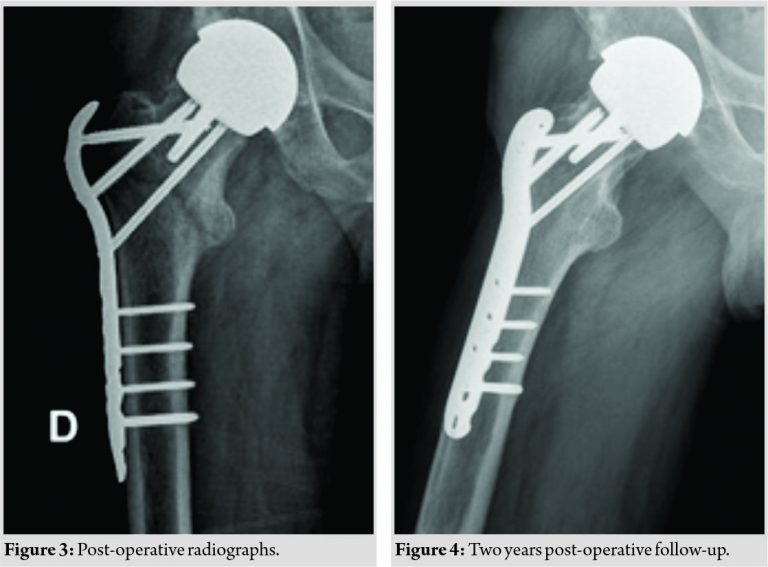

Open reduction and internal fixation of the fracture was then discussed with the patient, who consented. The fracture was reduced in a closed manner under general anesthesia on a traction table and internally fixed with the use of a 4.5mm LCP Proximal Femur Plate (SynthesDepuy, Johnson and Johnson, USA) (Fig. 3). The patient recovered without complication and was discharged 18 days after surgery, with instructions to walk with crutches and toe-touch weight-bearing for 8 weeks. Full weight-bearing started after 2 months. At the latest clinical review, 17 months after fracture, radiographs showed no complication related to either the resurfacing implant or the internal fixation. The patient reported only slight and occasional discomfort, which did limit activity. No plans have been made to remove the blade plate (Fig. 4).